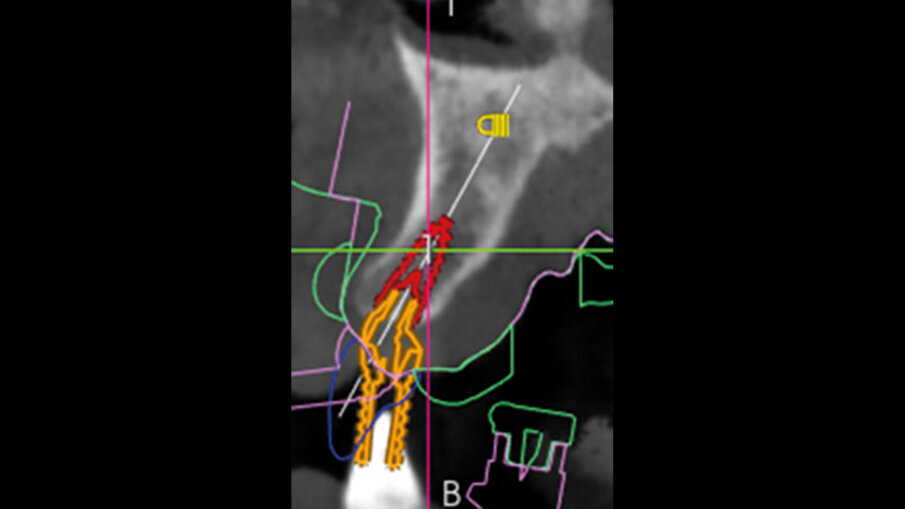

La pianificazione ha previsto innanzitutto l’allineamento all’interno del software dei file DICOM e dei file STL provenienti dalla scansione intraorale (Fig. 5). Il posizionamento degli impianti è stato ragionato in funzione di una ceratura diagnostica preventivamente realizzata con un CAD esterno e importata nel software di chirurgia guidata. Per la riabilitazione dell’arcata superiore, sono stati selezionati 6 impianti intercalati tra i siti post-estrattivi: 3,5 x 13 in posizione 11 e 22, 4 x 13 in posizione 24, 4 x 8 in posizione 26, 4 x 11,5 in posizione 14 e 4 x 10 in posizione 16. Utilizzando le informazioni dei modelli importati (master e ceratura) è stato possibile scegliere preventivamente anche le componenti protesiche in funzione delle emergenze rispetto alla ceratura e allo spessore dei tessuti (Figg. 6-8).